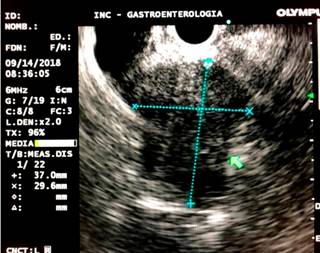

Con los hallazgos descritos se decidió el manejo paliativo y se llevó a CPRE con la intención de realizar una derivación biliar con stent; se encontró la papila distorsionada con retracción local de las paredes duodenales y se logró la canulación de la vía biliar distal, pero fue fallida para la vía biliar proximal. Entonces, se realizó la derivación biliodigestiva guiada por USE, en la que se encontró una infiltración neoplásica de la papila duodenal que impide su canulación y la cabeza del páncreas tenía una lesión hipoecoica heterogénea de 23 mm de diámetro con una dilatación retrógrada de la vía biliar hasta 18 mm (Figura 4). Se realizó una punción inicial de la masa para el estudio histológico y, posteriormente, de la vía biliar transduodenal con una aguja de 19 Fr, avanzando la guía hidrofílica 0,035; la dilatación se realizó con un balón dilatador biliar bajo control fluoroscópico y la posterior colocación del stent biliar metálico completamente cubierto de 10 x 80 mm, el cual se liberó bajo control endoscópico y fluoroscópico con una adecuada apertura y drenaje del medio de contraste y de bilis clara, sin complicaciones posteriores (Figuras 5 y 6). El reporte de la citología obtenida por endosonografía confirmó el compromiso por adenocarcinoma. A los 2 meses se le realizó control de bilirrubina total en 2,42 mg/dL; directa, en 1,85 mg/dL; e indirecta, en 0,58 mg/dL (Figura 7). La paciente continuó el manejo con oncología y cuidados paliativos.